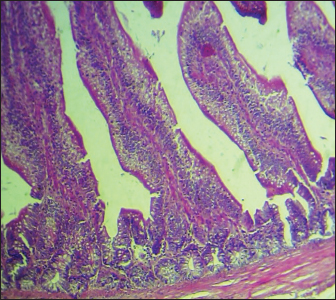

Histopathological study

The results noted in Figures 15 showed that chicks infected with S. enteritidis had edema among the muscular layer with atrophy of some intestinal villi. On the other hand, broilers infected with S. enteritidis and treated with C. myxa showed degeneration of intestinal glands with extensive inflammatory cell infiltration also mild sub-muscular edema, while with curcumin-treated group showed normal intestinal villi architectures, with hyperplasia of intestinal associated lymphoid tissue. The result noted a clear improvement in broilers that received C. myxa and curcumin showing normal intestinal villi with an increase in the number of goblet cells. The data of the present study confirmed the effectiveness of C. myxa and curcumin and especially the synergistic action between them in inhibiting the growth of S. enteritidis bacteria in poultry chickens, improving antioxidants and reducing free radicals, in addition to its action as a good anti-inflammatory at the blood level and suppressing the levels of cytokines that encourage inflammation and its role in improving intestinal tissues and making them close or similar to the health of broiler.

Fig. 1. Cross section of the intestine of poultry refers to normal histological architectures 100×. (H & E).

Fig. 4. Cross section of the intestine of poultry infected with S. enteritidis and treated with curcumin showing normal intestinal villi architectures, with hyperplasia of intestinal associated lymphoid tissue (200×, H & E).